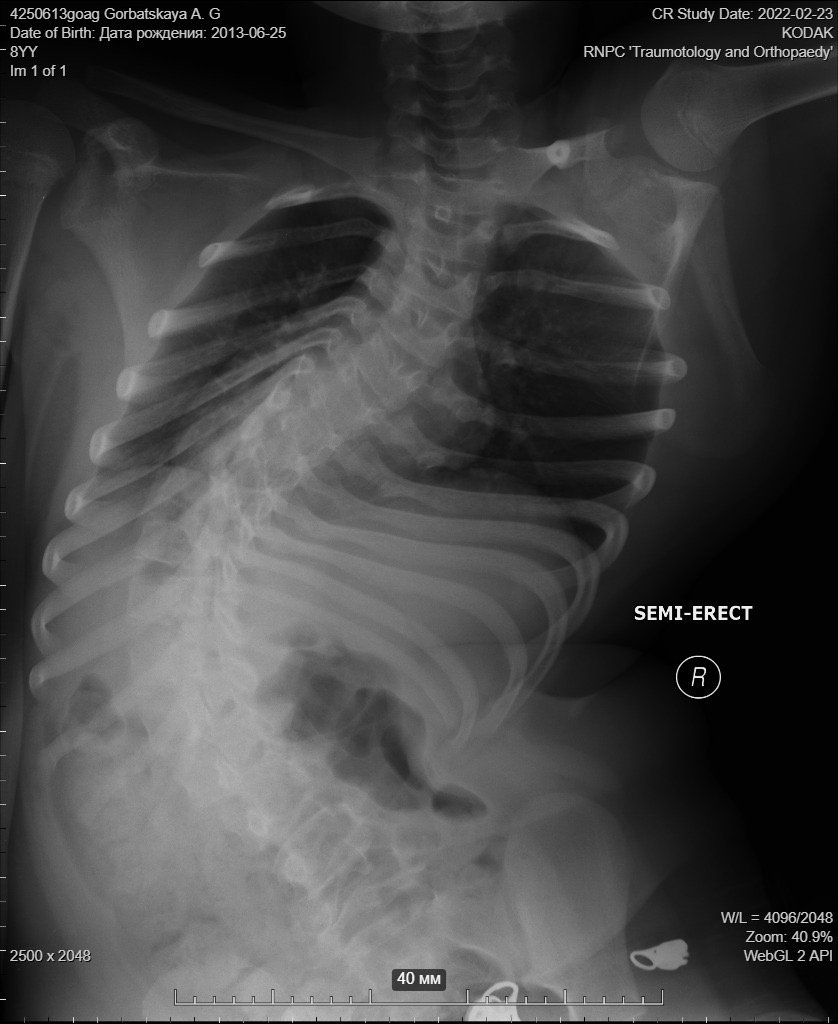

У одиннадцатилетней Анны Горбацкой (25.06.2013 г. р.) нейромышечный сколиоз на фоне ВПР спинного мозга.

Анна инвалид с детства, проживает в города Иваново Брестской области, самостоятельно не ходит. Когда была маленькая, носили на руках, делятся родители. Стала подрастать, и пересела в инвалидную коляску. Но тут начались проблемы со спиной.

Анна мечтает ходить самостоятельно, думали что вот-вот мечта станет реальностью. Но на консультации врачи не обнадежили, наоборот, сказали что ей срочно надо делать операцию. "Так как ребенок может умереть, потому что может передавить спинной мозг - это слова врача",- делятся родители Анны.

На фото рентген за 2022 год, сейчас еще хуже, говорят родители.